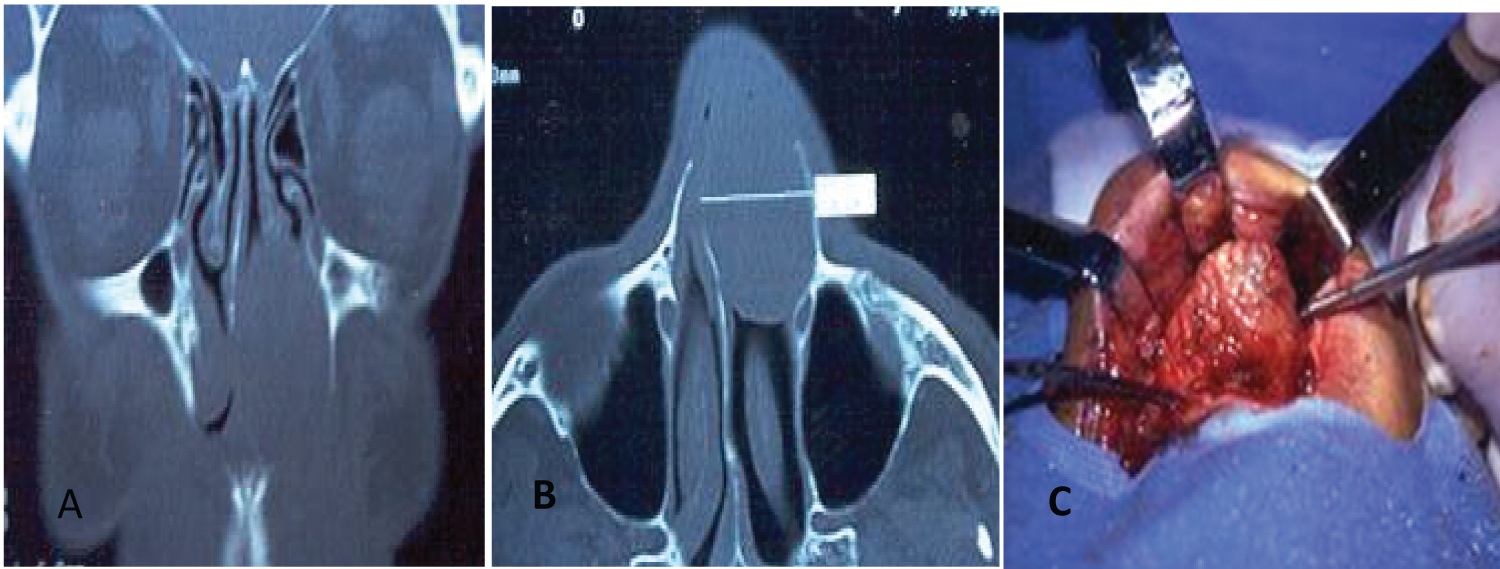

The surgical techniques used varied according to time, before the year 2000 the surgeries were performed using an external approach (Figure 1) or a combination of an external and endonasal approach (cranionasal with endoscopes in conjunction with the neurosurgeon) (Figure 2).

Figure1: Nasal cavity Schwannoma (A&B) Coronal and axial CT; (C) Sublabial approach. View Figure 1

Figure 2: Schwannoma with endocranial involvement and bilateral decrease in visual acuity (A) Coronal CT; B) Endoscope-assisted cranionasal resection: View from the craniotomy. View Figure 2

Reconstruction of the skull base was done with a pericranium flap.